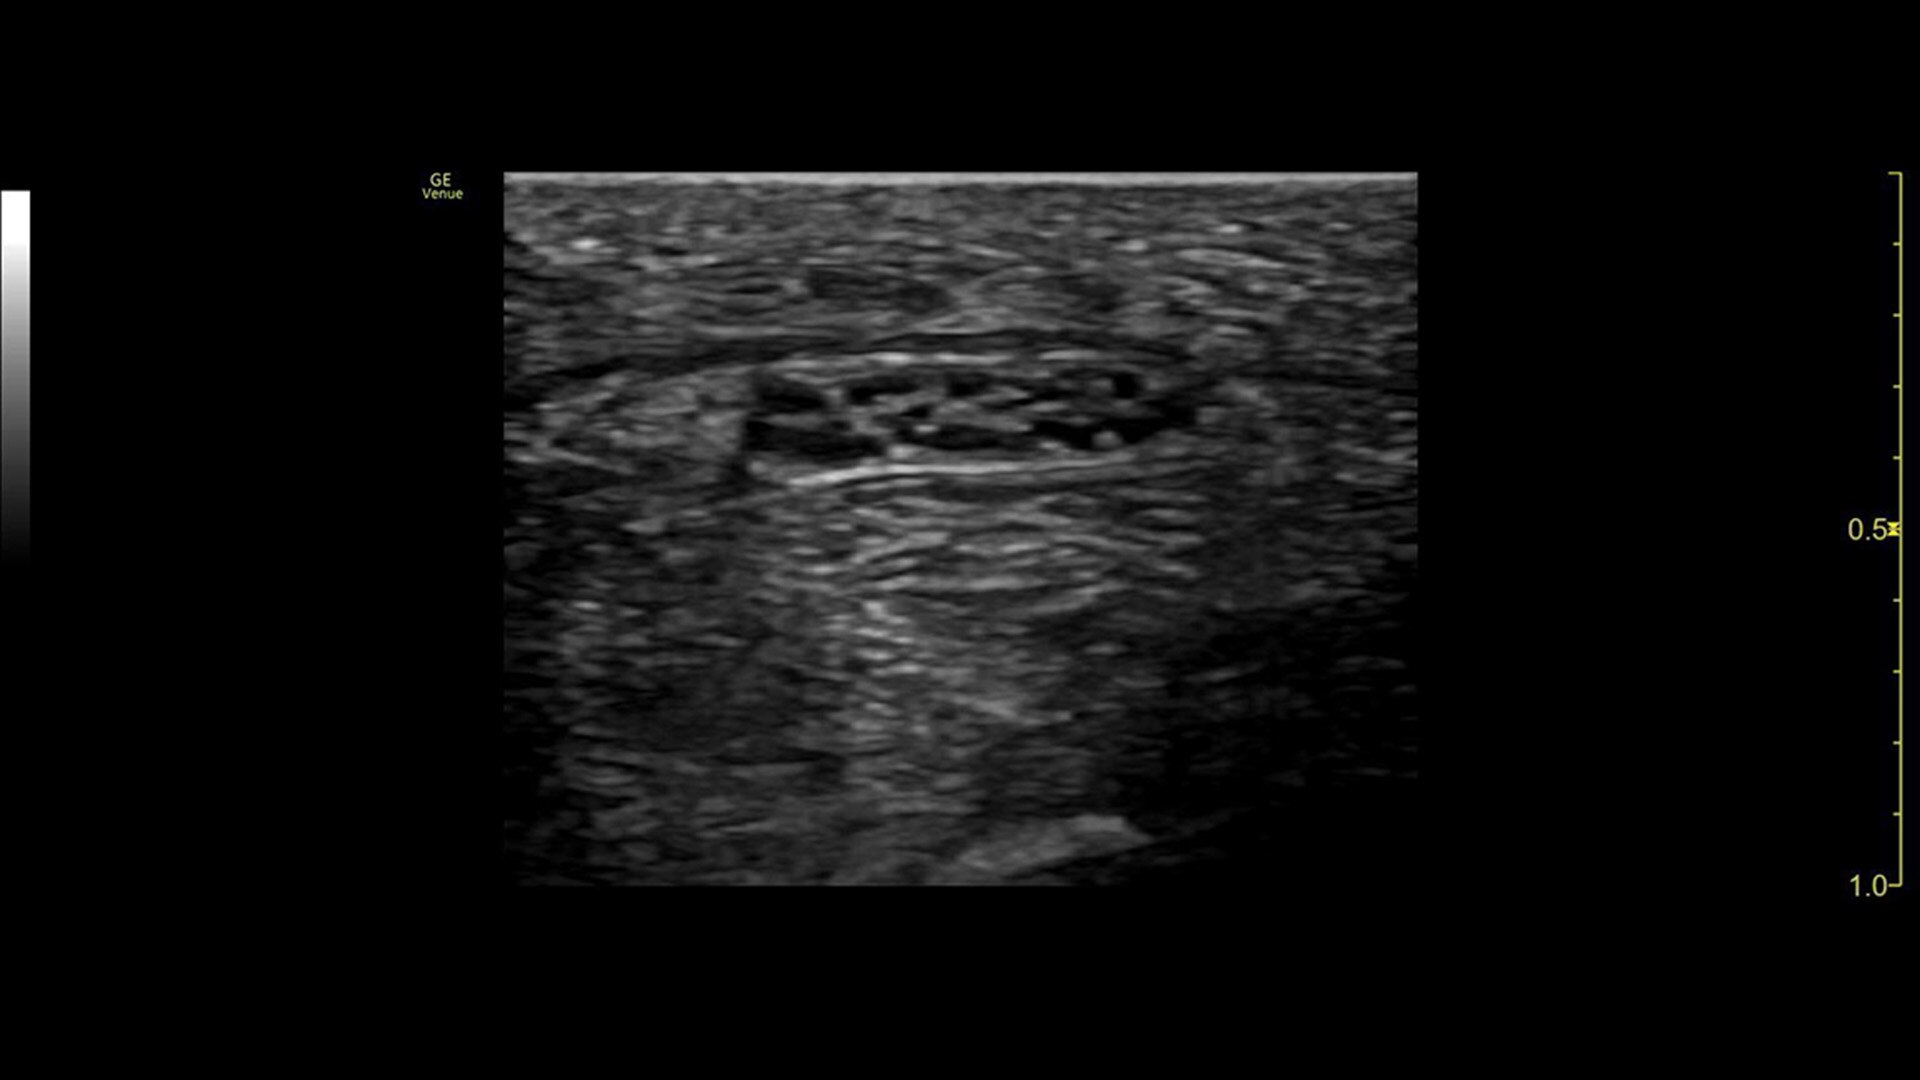

Follow nerve block procedures with cNerve

Helps detect and track nerves in 99% of cases during live scanning or while reviewing a stored clip2 while also displaying a distribution map of the areas on the body impacted by the selected nerve block procedure.